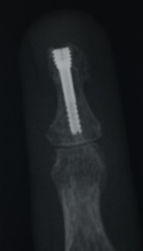

Distal falanks, parmak ucundaki kemiktir. Uygun parmak fonksiyonu ve tırnak büyümesi için sabit bir distal falanks gerekir. Çoğu distal falanks kırığının düzeltilmesi gerekmezken, bazılarının düzeltilmesi gerekir. Bunlar, düzgün bir şekilde birleştirilmesi gereken birçok parça ile oldukça karmaşık olabilir. Kötü bir şekilde düzeltilmiş kırıklar iyi iyileşmez, çok fazla ağrıya neden olur ve işe dönüşü geciktirir.

Eldeki kapalı kırıklar, yerinden oynamışsa veya deformiteye neden oluyorsa, uygun hizaya geri konulmalı ve ele iyi bir fonksiyon kazandırmak için metal teller, vidalar veya plakalarla sabitlenmelidir. Bu, el yaralanmasından birkaç gün sonra, mümkün olan en kısa sürede erken rehabilitasyona izin vermek için en iyi şekilde yapılır.